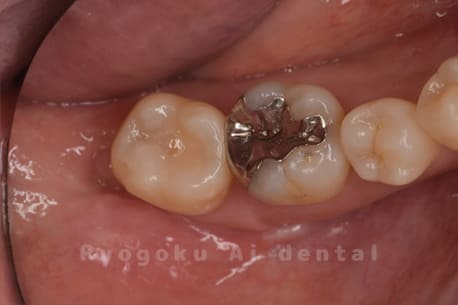

Case14

-

- 抜歯原因

- 重度カリエス

- 治療内容

- クラウンレングスニング治療

- 治療費用

- 44,000円

他院で抜歯と言われた、とのことでご来院された患者さまです。クラウンレングスニングを行い、保存致しました。大変満足して頂けました。

<リスク・副作用>

治療後、痛みや違和感、出血、腫れなどが出る事があります。喫煙者、糖尿病などの方の場合、歯が生着しない場合があります。